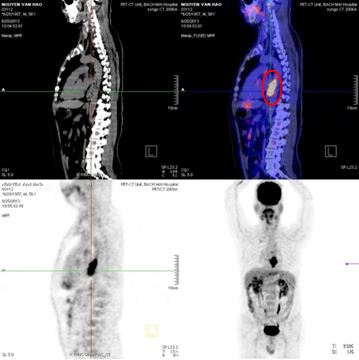

Hình 1: Hình ảnh nội soi dạ dày có hình ảnh u sùi loét 1/3 giữa thực quản-viêm dạ dày

- Bệnh nhân được chụp cắt lớp vi tính lồng ngực: Kết quả cho thấy

Dày không đều thành thực quản đoạn 1/3 giữa dưới, lồi vào trong lòng gây hẹp lòng thực quản, không đánh giá được hạch trung thất.

Hình 2. Hình ảnh khối u 1/3 giữa thực quản, gây hẹp lòng thực quản